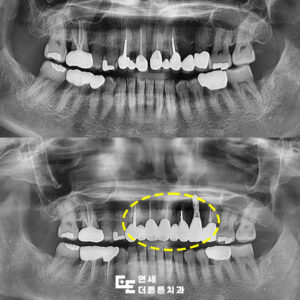

망월사역치과 변색된 아래 앞니 브릿지 수복

망월사역치과 변색된 아래 앞니 브릿지 수복 치아는 음식물을 씹고 끊는 저작기능 외에도 외모에 중요한 영향을 미치며 특히 앞니는 잘 드러나기 때문에 색상이나 배열이 좋지 않으면 타인에게 부정적인 인상을 줄 수 있습니다. ​ 이에 따라 보철치료가 필요할 때가 있는데 이를 고려하기 전에는 반드시 확인해야 할 중요한 사항들이 몇 가지 있습니다. ​ 더보기…